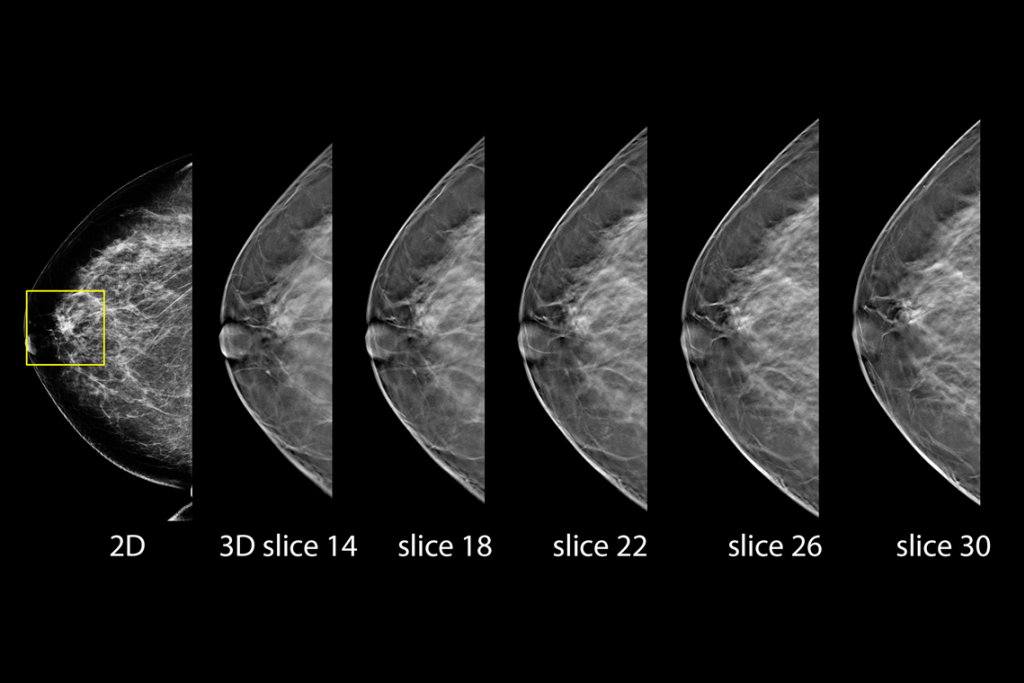

Immagini cliniche di una mammografia

Immagini cliniche di una mammografia con lesione sospetta

Immagini cliniche di una mammografia con tessuto mammario denso